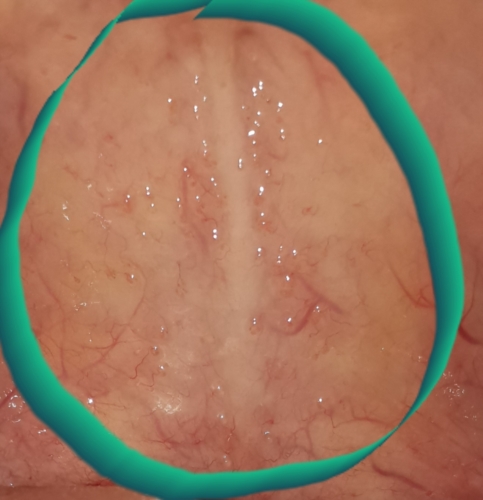

i have noticed rough soft palate from 2 months.tiny,multiple painless,firm bumps present on soft palate,near gums.dermatologist suspecting oral warts,ent doctor didnt comment about warts. can anyone please tell what they are.

my voice also changed.anterior tonsillar area is white and inflammed.not responding to antibiotics.please comment your opinion.

I'm pretty sure these are clogged saliva ducts. Try sucking on a lemon and the clog should unclog. I had them too and they went away after a couple weeks.

also seek the help of a dentist, that's who diagnosed mine. They should know just by looking at it. A dentist will know more about the mouth then a dermatologist.